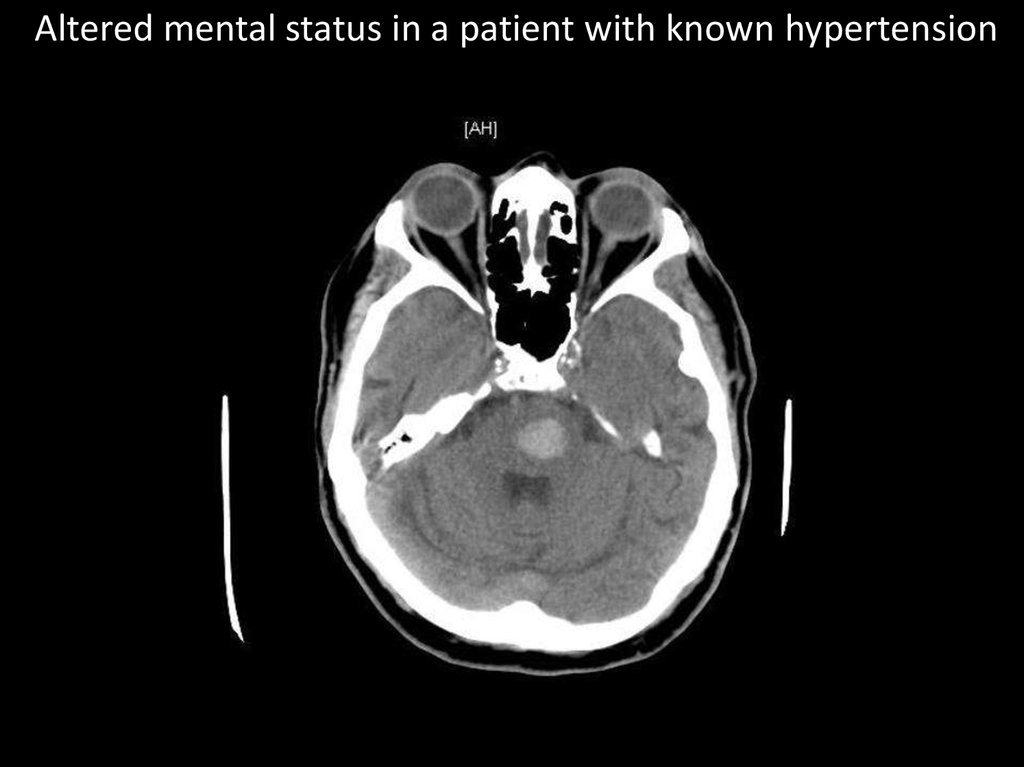

Altered mental status in a patient with known hypertension